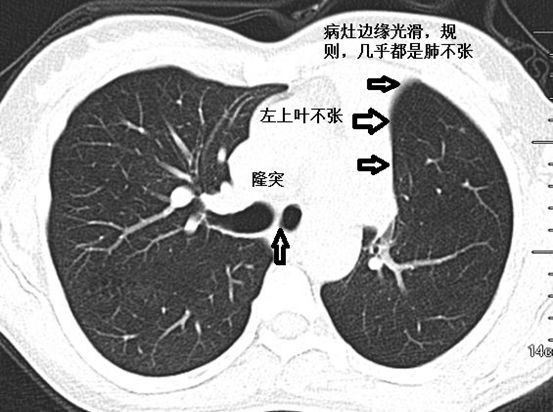

肺不张ct读片太难?看完这篇文章轻松入门!

肺不张影像基本思路

肺不张ct读片太难看完这篇文章轻松入门

轻松搞定肺不张,肺ct入门难点之一